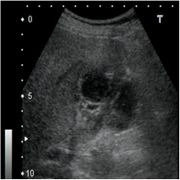

[黄色肉芽腫胆嚢炎] 手術:胆嚢摘出術(結腸切除術併施)

血液検査にて炎症反応の上昇を認め、精査の結果、急性胆嚢炎と診断。胆嚢摘出術(結腸切除術併施)を施行した。病理結果は黄色肉芽腫胆嚢炎であった。

超音波画像